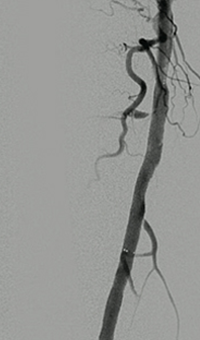

Venous thrombosis extending from popliteal to external iliac vein

Extensive DVT of the right common femoral and external iliac was treated with the 8 F AngioJet™ ZelanteDVT™ catheter.

Patient history

73 year old with 1-week old right leg swelling and pain.  Started on anticoagulation and discharged.

Consult confirmed extensive DVT from popliteal extending into external iliac vein.

Procedural steps

• Power Pulse ( tPA 10 mg in 50 cc)

• Patient put on 2-hour lytic catheter drip in holding area

• Thrombectomy performed with 8F ZelanteDVT catheter

• Directional ability of ZelanteDVT allowed targeting of residual thrombus in Popliteal and Superficial Femoral Vein Post Venography shows complete resolution of thrombus

xray of occlusive thrombus extending into the iliac vein.

Occlusive thrombus extending into the iliac vein

xray of femoral vein pre-treatment.

Femoral vein pre-treatment